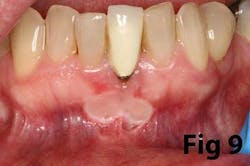

There is an abundance of literature showing increased gingival inflammation around natural dentition (exacerbated when a fixed restoration is present) when there is less than 2 mm AG. (Figs. 8, 9: post grafting) There is an abundance of literature showing increased incidence of peri-implant mucositis when there is inadequate attached tissue — a weaker connective tissue adhesion and lack of Sharpey’s fibers make the peri-implant tissue even more susceptible to bacterial challenge. (1-6, 8, 10) And as periodontitis is always preceded by gingivitis, peri-implantitis will be preceded by peri-implant mucositis. If we can decrease the incidence of peri-implant mucositis by providing a better and more resilient tissue phenotype, we can lower the incidence of peri-implantitis.The FGG procedure is indicated in cases of implant therapy where this is less than 2 mm of attached tissue present. Sometimes, a FGG is preferred over CTG because: (1) the FGG results in greater gain of attached tissue, (2) the FGG alleviates frenum/muscular pull whereas the connective tissue may increase muscular tension after the flap is coronally advanced, and (3) creeping attachment is often a positive byproduct of the FGG procedure.